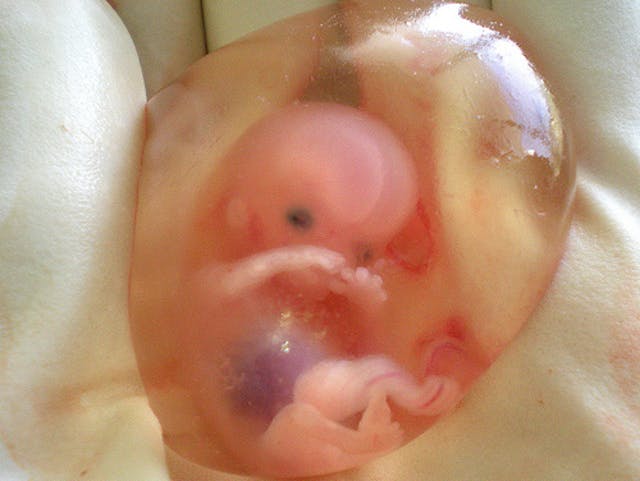

It really is mind-blowing to learn about the development of preborn children. According to the Endowment for Human Development, which released a prenatal video series in partnership with National Geographic, by nine weeks after fertilization (according to six different studies), “the nerve receptors in the face, palms of the hands, and soles of the feet can sense and respond to light touch. Following a light touch on the sole of the foot, the fetus will bend the hip and knee and may curl the toes.” Between 12 and 13 weeks after fertilization (according to three different studies), the preborn child’s “whole body surface, except the top of the head and the back, responds to light touch.” By 24 weeks in the second trimester, the preborn baby “responds to pressure, movement, pain, hot and cold, taste, and light.”

READ: First trimester babies aren’t blobs of tissue — they’re amazingly complex